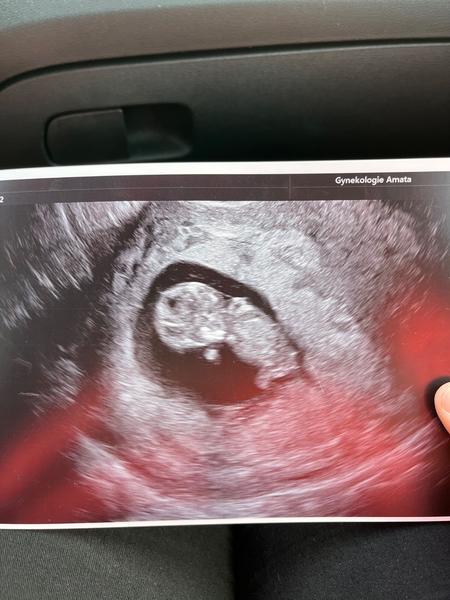

@kristynaprandl no to já jsem také zvědavá 🥰 tak na kontrole vse v poradku. Miminko je sice o 5 dní mladší,ale to vůbec nevadí. Krasne si tam kopalo a mavalo ručičkama🥰❤ ultrazvuk ma teda hroznou kvalitu,ale nevadí taky fotečka 🥰